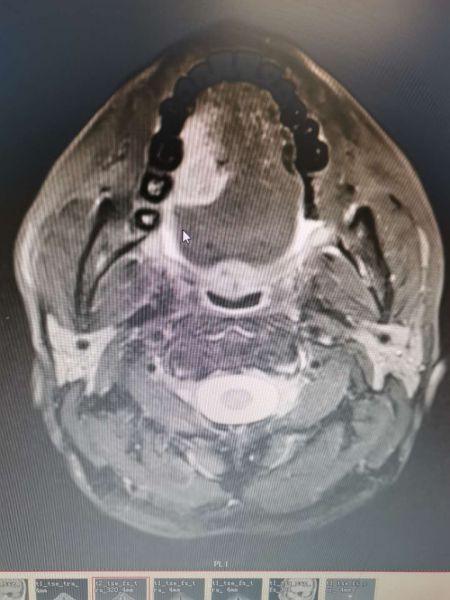

守护人民群众生命安全和身体健康也是每一个医护人员的初心。正月初六,还没正式上班,科室来了一位因舌溃疡伴疼痛就诊的患者,据门诊磁共振显示:“考虑舌Ca可能性大,范围30mmx18mmx24mm”。

术前,在科主任、副主任、主治医师等人共同研讨下制定多套治疗方案并得出结论:患者因舌癌范围大,术中沿肿瘤外周再扩大切除1.5cm,意味着要切除半个舌头及口底,修复重建有很大困难和风险,若考虑前臂游离皮瓣较薄,修复口底没肌肉充填,术后易形成口底瘘,而取胸大肌带蒂皮瓣修复舌缺损,可能会影响舌体活动度。最后大家认为股前外游离皮瓣是最适合的,但科室自主从未制取先例,而且很容易在制取股前外游离皮瓣或动静脉血管吻合过程中出现特殊情况造成整个手术失败,风险及并发症极大。这时,科室主治医师盘和主动请缨并自信道:“总会有第一次的,请放心让我取瓣吻血管吧”。

在排除新冠肺炎的前提下,于正月十二开展了这一肿瘤限期手术。期间,手术历时9小时,进行右舌口底癌扩大切除术+颌骨固定内固定术+右颈部淋巴结清扫术+左侧股前外游离皮瓣转移修复术+微动静脉血管吻合术+气管切开术。手术顺利,完成了口腔科此类病例的突破,术后,经对症支持治疗,皮瓣成活,患者半月后康复出院。